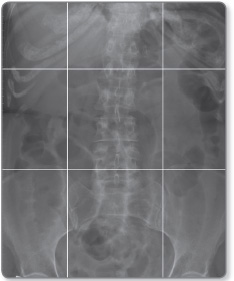

For convenience the abdominal cavity is divided into nine segments (Figure 1.1). These regions can be demarcated on an abdominal radiograph by drawing a horizontal line through the 9th ribs and the pelvic brim, and two vertical lines from the centre of the costal cartilage of the 9th rib to the middle of the inguinal ligament. The organs (Figure 1.2) contained in these segments are as follows: